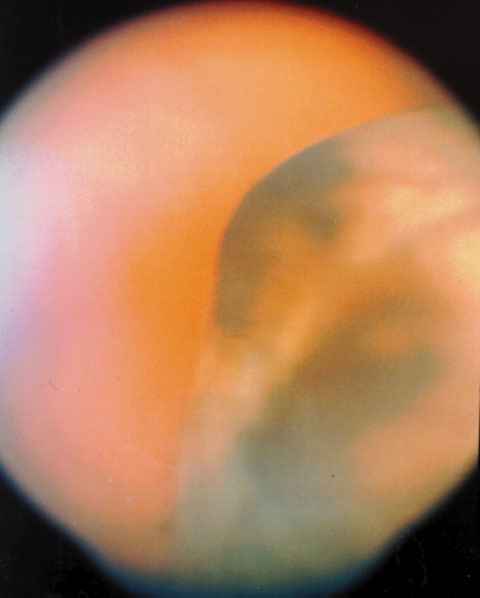

Figura 6

MELANOMA DE COROIDES.